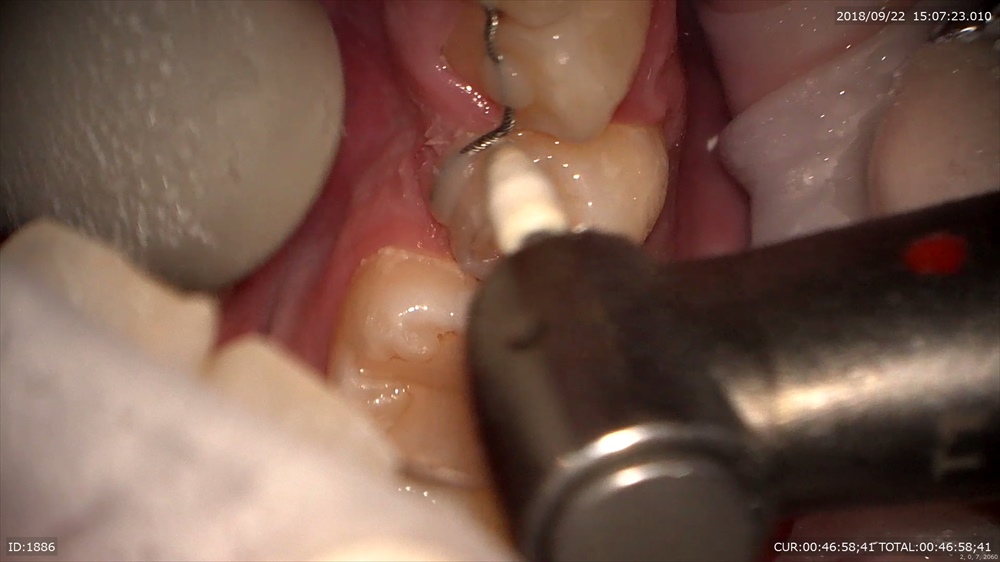

研磨も直視

EXTARO300かなり良いです。矯正のブラケットセットにも向いているなー。

根管治療

レンズが良いので難治性の治療も根尖をみてデブライドメント